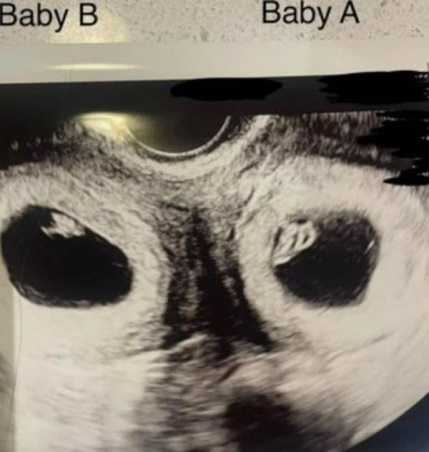

醫生建議她可以做試管嬰兒試試看,終於在2年9次的嘗試後成功懷孕,沒想到醫生幫她做產檢時,驚訝發現她懷上了雙胞胎,而且兩邊子宮還同時懷孕,最離奇的是,一邊是試管嬰兒,一邊是自然受孕,這種機率只有5千萬分之一!

(圖片來源:9now.nine.com.au)